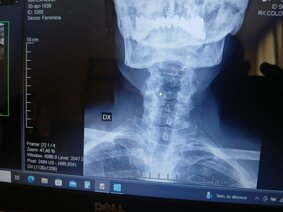

SCHIENA: Rachide cervicale

Trattamento con fisioterapia della cervicalgia e

cervicobrachialgia e patologie secondarie ed esse